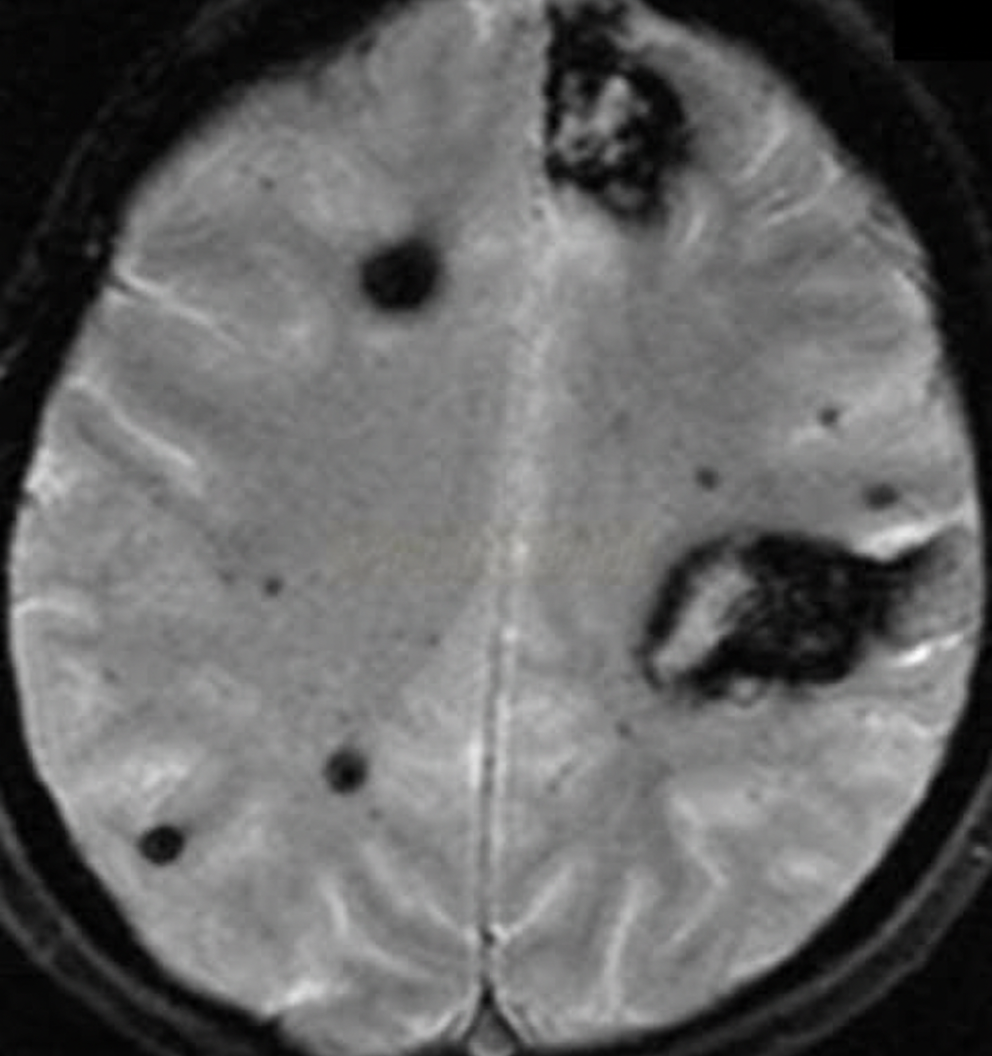

An 88-year-old woman with no significant medical history is brought to the emergency room by her daughter after a fall, where the woman lightly hit her head against a wall. The patient is lucid and complains of a mild headache. The daughter indicates that her mother did not lose consciousness after the fall. On exam, there are no focal neurological deficits, but you decide to perform a CT scan to be sure there is no intracranial bleeding. The CT scan is within normal limits and head MRI is performed (shown). Which of the following conditions has the most similar risk factor to this patient's condition?